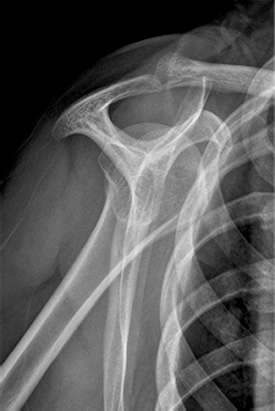

-X-Quang Y view: xem hình dạng của mỏm cùng vai

Hình 8: Hình X-Quang Y view